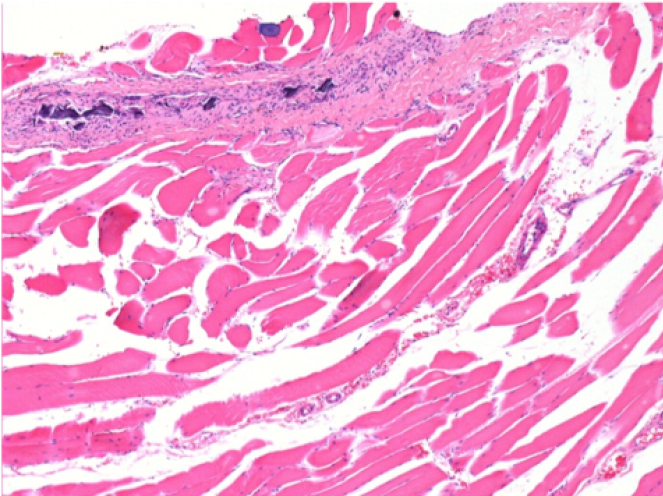

10 días después de la inyección de Endopeel

10 días después de la inyección de Endopeel 0,1 ml en el músculo pretibial derecho.

Aquí puede ver la formación de las vacuolas que están rodeadas de linfocitos. Las vacuolas son diferentes a la necrosis tisular. La presencia de linfocitos está relacionada con la permeabilidad de las membranas celulares.

L : Control-100xD10

R:100xD10

R :200xD10

R :400xD10